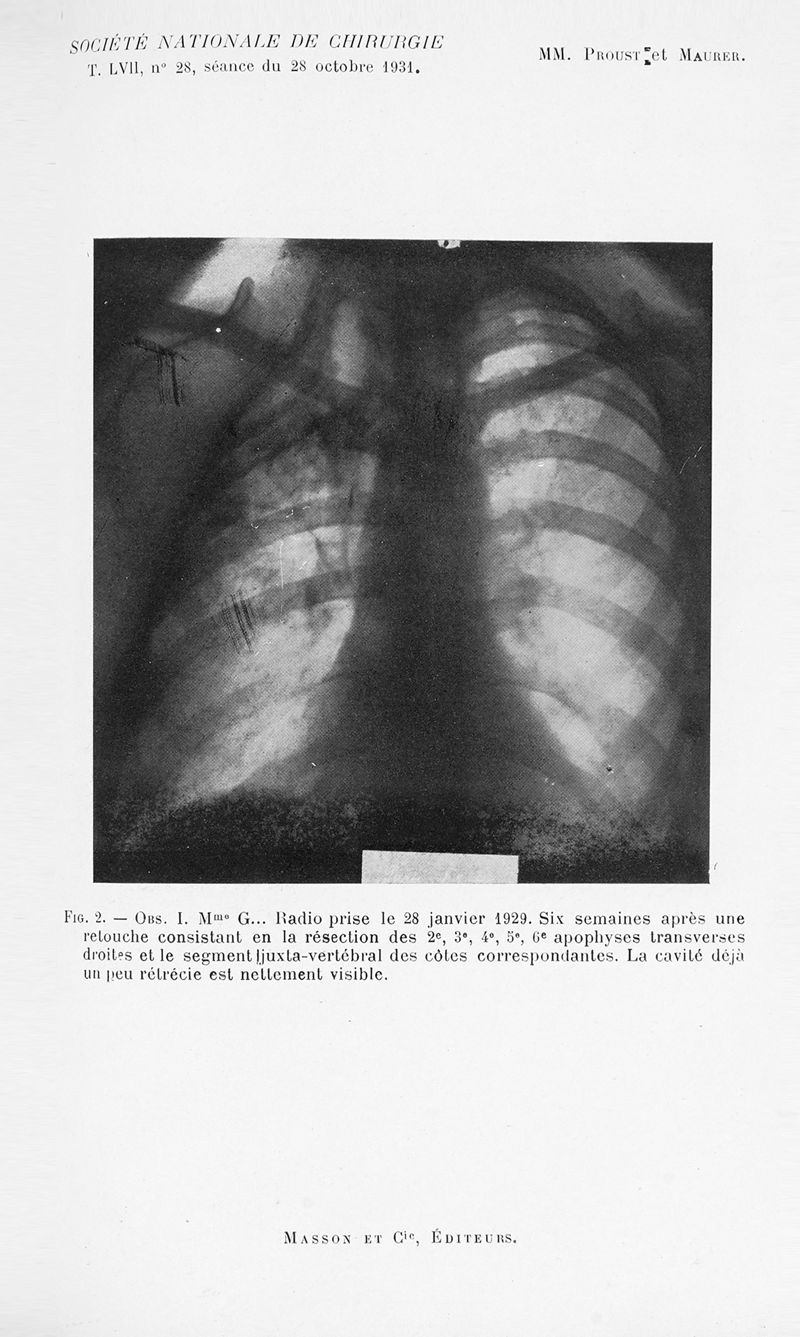

Bulletins et mémoires de la société nationale de chirurgie

Tome LVII, 1931. - Paris : Masson, 1931.